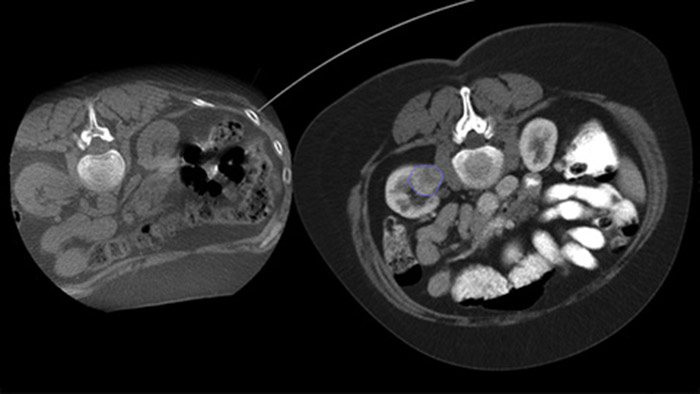

Mit Dual View kann ein 3D-Vorabbild (CT/MR/PET-CT) über ein intraprozedurales 3D-CBCT-Dual-Bild gelegt werden, um die Läsionen besser sichtbar zu machen und entscheidende Informationen für die Nadelplanung zu erhalten.

Die perkutane Ablation (Hochfrequenz-, Mikrowellen- und Kryoablation) ist eine etablierte, minimal-invasive Behandlungsmethode für Nieren-, Leber-, Lungen- und Knochentumore. Dabei ist es besonders wichtig, den Tumor abzugrenzen und eine geeignete Anzahl an Nadeln und notwendigen Nadelverläufen festzulegen, damit der gesamte Tumor behandelt werden kann, ohne das umliegende Gewebe zu schädigen. Durch die präzise Navigation zur relevanten Läsion bei niedriger Strahlendosis und ohne Neupositionierung der Nadel werden die Erfolgschancen erhöht und das Komplikationsrisiko bei Biopsien und Ablationen reduziert. Der Endpunkt der Ablationsbehandlung kann mittels 3D-Bildgebung verifiziert werden, während sich der Patient noch auf dem Tisch befindet.